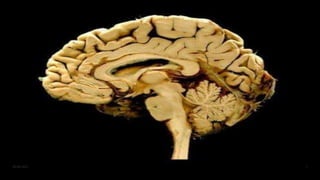

Anatomy of brain

06-08-2021 4